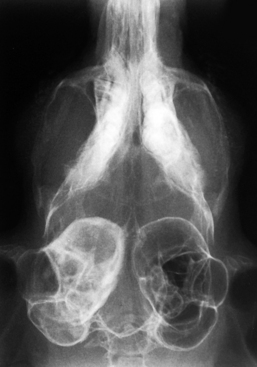

Poruchy při porodu

U činčil se nejčastěji vyskytují různé problémy při porodu.

Symptomy: Březí činčila ve vysokém stupni březosti je apatická, nekomunikativní, nebere si potravu, sedí neustále na jednom místě, snaží se vyvolat porod tlačením. Sedí sklesle a nebo leží na boku.

Možné příčiny: Příčinou mohou být příliš velké plody, plody nacházející se pouze na jedné straně v děloze samičky, nekróza v těle samičky, letální faktor, porody po 3 měsících - tedy ihned po sobě, nebo připuštění samičky v moc mladém věku. Pokud se plody vyskytují pouze na jedné straně, nebo jsou příliš velké, samice není schopna mláďata porodit.

Léčba: Chybné polohy plodů, nebo velké plody Ize diagnostikovat rentgenologicky. Pokud přetrvává apatie u samice a stále se nerodí mláďata, je nutné ihned vyhledat veterináře specializovaného na porody drobných savců. Veterinář provede císařský řez. S tímto je ovšem spojena i kastrace samice. Pokud je v těle činčily nekróza, je potřeba ihned nekrotickou část vyoperovat. Často ovšem pro samičky bývá pozdě, jelikož se často nekróza utvoří ještě před porodem. Letální faktor je faktor kdy mládě není schopno života díky nefunkčním některým funkcím důležitým k životu. Tento faktor se nalézá v genech bílých činčil a v genech činčil se znaky velveta. U každé této mutace se ale vyskytují na jiném lokusu a proto se mohou křížit bílé činčily s velvety, ale ne bílá x bílá či velvet x velvet. U bílých činčil se nejčastěji stane, že mládě zemře ihned po porodu nebo ještě v těle matky a ta jej buďto porodí mrtvé nebo vlivem nekrózy tělíčka v těle matky zmírá i matka. U velvetů samice často plody potrácejí, tedy narodí se předčasně mrtvé. Toto se může dít i u neletálních činčil právě vlivem ostatních příčin.

zde porozená siamská dvojčata přirostlá bříšky, která matka nemohla vytlačit kvůli velikosti plodu. Mláďata nepřežila.

Snímek se 3 mláďaty

zdroj: Buyxraysonline